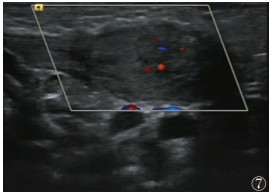

20例CMT合并DDH中,左侧CMT伴DDH者11例(图 7),其中左髋DDH 6例,右髋DDH 1例,双髋DDH 4例;右侧CMT伴DDH者9例(图 8),其中左髋DDH 2例,右髋DDH 5例,双髋DDH 2例。CMT与DDH损害方向在同侧11例,对侧3例,双侧6例,CMT与合并的DDH方向无关(χ2=0.900,P=0.638)。

| 图 7 男,56 d,左侧先天性肌性斜颈(CMT)(肿块型)声像图:左侧胸锁乳突肌(SCM)见梭型低回声团,大小24 mm×11 mm,肌纹理紊乱,内回声不均匀,可见点状血流信号 |

目前,超声已被认为是诊断CMT和DDH最敏感的工具之一,并被广泛用于两者的诊断[2, 13]。一方面,超声可用于量化CMT患儿肌肉纤维化程度,确定肿块的大小和位置,并指导临床制订治疗方案[17]。本组非肿块型98例,肿块型78例。非肿块型常仅表现为头歪向一侧,此时运用超声测量双侧的SCM的厚度、对比是否有局限性增厚,观察肌纤维排列、肌纹理回声及与周围组织关系从而早期诊断CMT;对于肿块型,超声可明确肿块来源,排除淋巴管瘤、淋巴结等其他颈部肿块。根据患侧SCM的声像图特点推测肌肉纤维化程度,从而选择治疗措施,并通过超声计算出SCM挛缩长度、确定临床手术方案和松解范围[1, 18-21]。此外,超声在后期疗效观察和判断预后上也有重要价值,通过测量治疗前后SCM厚度、肿块大小,以及观察病变区血流情况,有利于评估CMT疗效。另一方面,相对于体格检查较明显的CMT,DDH可能更易忽视;尤其6个月以内的婴幼儿,因髋臼软骨未骨化X线不能显像,早期诊断DDH更困难。而超声波可穿透软骨,清晰显示关节囊、关节盂唇、股骨头软骨及髋臼等解剖结构;其中Graf超声静态测量方法因敏感性高,且观察者间的图像采集测量解读差异小、可重复性较高等优点,能更早期发现DDH,在婴儿髋关节超声检查中最普及[16, 22-23]。本组176例CMT患儿,通过Graf方法对髋关节进行分型,显示并发DDH 20例(40髋),其中Ⅰ型14髋(35.0%)、Ⅱa型17髋(42.5%)、Ⅱb型5髋(12.5%)、Ⅱc型1髋(2.5%)、Ⅲ型2髋(5.0%)、Ⅳ型1髋(2.5%),临床上根据具体病理阶段选择和实施合适的治疗,病情均得到不同程度的改善、获得满意的治疗效果。此外,应用彩色多普勒超声还可监测DDH治疗过程中股骨头血供情况,以减少股骨头坏死的发生[24]。